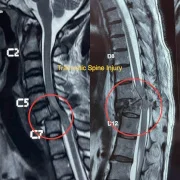

We provide urgent and effective spinal fracture treatment in Thane, offering immediate care for traumatic spine injuries caused by accidents, falls, or osteoporosis. Our trauma team specializes in stabilization surgeries, vertebroplasty, kyphoplasty, and minimally invasive fixation techniques to restore spinal alignment and prevent neurological complications. With 24×7 neuro-spine emergency care, patients receive immediate treatment and rehabilitation support.

– Traumatic Spine Injury